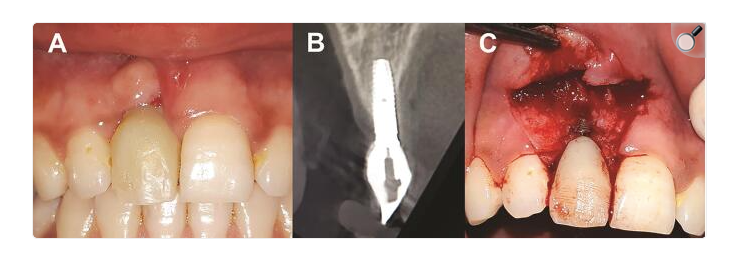

În practica clinică, delimitarea dintre mucozita periimplantară și periimplantita este rareori suficientă pentru a ghida singură decizia terapeutică. Evaluarea corectă presupune integrarea unor criterii clinice obiective, care permit aprecierea severității bolii și alegerea unei abordări adaptate fiecărui caz.

Sursa foto: PMC7536094

Criterii clinice care ghidează decizia terapeutică în periimplantită

Stabilirea conduitei terapeutice în periimplantită pornește de la evaluarea unor criterii clinice care reflectă activitatea bolii și limitele tratamentului non-chirurgical. Aceste repere permit clinicianului să aprecieze dacă măsurile conservative pot asigura controlul inflamației sau dacă este justificată luarea în considerare a unei abordări chirurgicale, conform recomandărilor actuale ale ghidurilor Federației Europene de Parodontologie (EFP).

Un criteriu central îl reprezintă adâncimea pungilor periimplantare la sondare (probing pocket depth – PPD). Pungile adânci, persistente, mai ales după o etapă inițială de tratament non-chirurgical, indică dificultăți reale în obținerea unei decontaminări eficiente a suprafeței implantului. Accesul limitat la zonele contaminate favorizează persistența biofilmului și explică rezultatele clinice modeste raportate pentru terapiile fără lambou în formele moderate și avansate ale bolii.

Sângerarea la sondare (bleeding on probing – BoP) și supurația oferă informații suplimentare despre activitatea inflamatorie. Prezența lor constantă sugerează un proces inflamator activ și un risc crescut de progresie, mai ales atunci când este asociată cu valori crescute ale PPD. Aceste semne clinice trebuie interpretate integrat, în corelație cu datele radiologice, pentru a aprecia corect severitatea bolii.

Pierderea osoasă periimplantară documentată radiologic reprezintă un criteriu definitoriu în diferențierea mucozitei periimplantare de periimplantită. Identificarea unei pierderi osoase progresive, dincolo de remodelarea inițială post-inserare, indică depășirea fazei reversibile a inflamației și limitează predictibilitatea tratamentului exclusiv non-chirurgical.